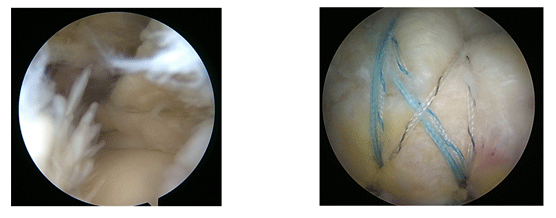

°üÀý°æ(°üÀý ³»½Ã°æ) ¼ö¼ú

°üÀý³»½Ã°æ ¼ö¼úÀº ¹®Á¦°¡ »ý±ä °üÀý ºÎÀ§¿¡ 1cm ¹Ì¸¸ÀÇ ±¸¸ÛÀ» ³»°í Ä«¸Þ¶ó°¡ ´Þ¸° °üÀý³»½Ã°æÀ» »ðÀÔÇØ °üÀý »óŸ¦ ¸ð´ÏÅÍ·Î º¸¸é¼ °üÀý ¼ÓÀ» Á÷Á¢ °üÂûÇϰí ÃËÁö ÇØº¸¾Æ º´º¯À» Ä¡·áÇÏ´Â ¼ö¼úÀÔ´Ï´Ù. ¸ð´ÏÅ͸¦ ÅëÇØ °üÀý ¼ÓÀ» È®´ëÇØ º¼ ¼ö Àֱ⠶§¹®¿¡ ´õ¿í Á¤È®ÇÑ Ä¡·á°¡ °¡´ÉÇϸç MRI °°Àº Ư¼öÃÔ¿µÀ¸·Îµµ ÆÄ¾ÇÇÏÁö ¸øÇÑ Áúȯ »óűîÁö Á¤È®È÷ Áø´ÜÇØ ¼ö¼úÇÒ ¼ö ÀÖ½À´Ï´Ù. ¼ö¼ú½Ã°£ÀÌ Âª°í Àý°³ ºÎÀ§°¡ ÀÛ´Ù º¸´Ï °¨¿° °°Àº ¼ö¼ú ÈÄÀ¯Áõ°ú ¼ö¼ú ÈÄÀÇ ÅëÁõÀÌ ÀûÀ¸¸ç, ÀÔ¿ø±â°£ ´ÜÃàÀ¸·Î ºñ¿ëµµ ÁÙÀÏ ¼ö ÀÖ´Â °Ô Å« ÀåÁ¡ÀÔ´Ï´Ù. ƯÈ÷ ÈäÅͰ¡ °ÅÀÇ ³²Áö ¾Ê¾Æ ¹Ì¿ëÀû Ãø¸é¿¡¼ ÀþÀº »ç¶÷µé¿¡°Ô °¢±¤¹Þ°í ÀÖ½À´Ï´Ù.